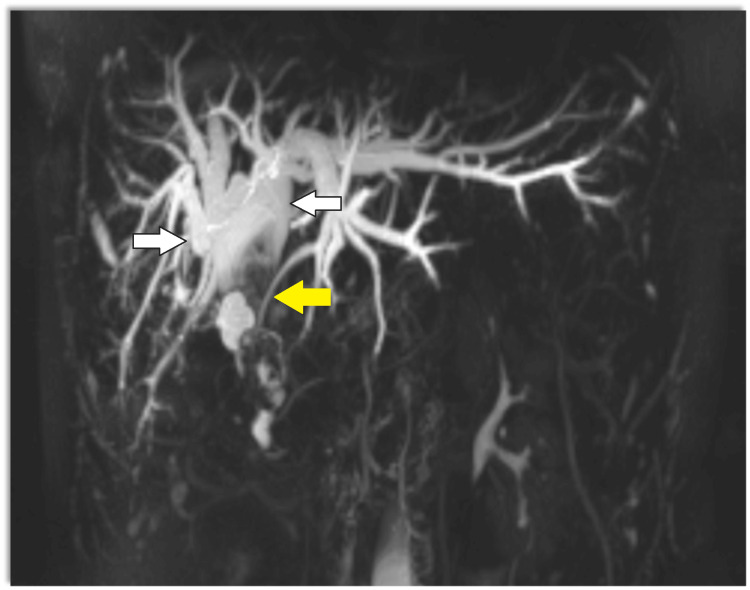

Magnetic resonance cholangiopancreatography (MRCP) showed dilatation of bi-lobar intrahepatic biliary radical (IHBR) with dilatated CBD large T2 hypointense and T1 (Figure 1), hyperintense calculus is seen, occupying dilated CBD and common hepatic duct (CHD). It extends into the left hepatic duct (LHD) and right hepatic duct (RHD), with the possibility of type 1c choledocholithiasis with cystolithiasis, and hepatolithiasis with cholelithiasis (Figures 2, 3).